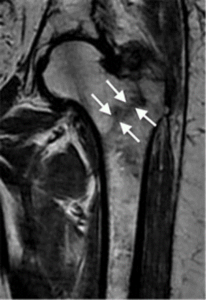

A hip fracture involves damage to one of the four key regions of the upper femur:

- Femoral Neck: Located just beneath the femoral head (the ball), this area connects the head to the shaft of the femur.

- Intertrochanteric Region: This is the area between the femoral neck and the shaft, defined by two prominent bony structures — the greater and lesser trochanters.

Among these, intertrochanteric fractures and femoral neck fractures are the most frequently occurring types of hip fractures. On the other hand, femoral head fractures are exceedingly rare, often resulting from high-impact injuries like car accidents or severe falls.